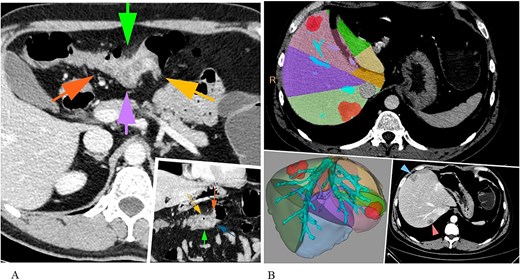

The second (transverse colon) surgical stage demanded to reverse the patient’s position to supine. Two additional trocars were placed: 5 mm right paraumbilically and 5 mm infraumbilically (Fig. 3). A transverse colon resection was performed, followed by an extracorporeal, hand-sutured end-to-end colon anastomosis (Video).

Graphic representation of the patient's positioning on the operating table (supine position) during colon resection and final view on the fifth postoperative day.